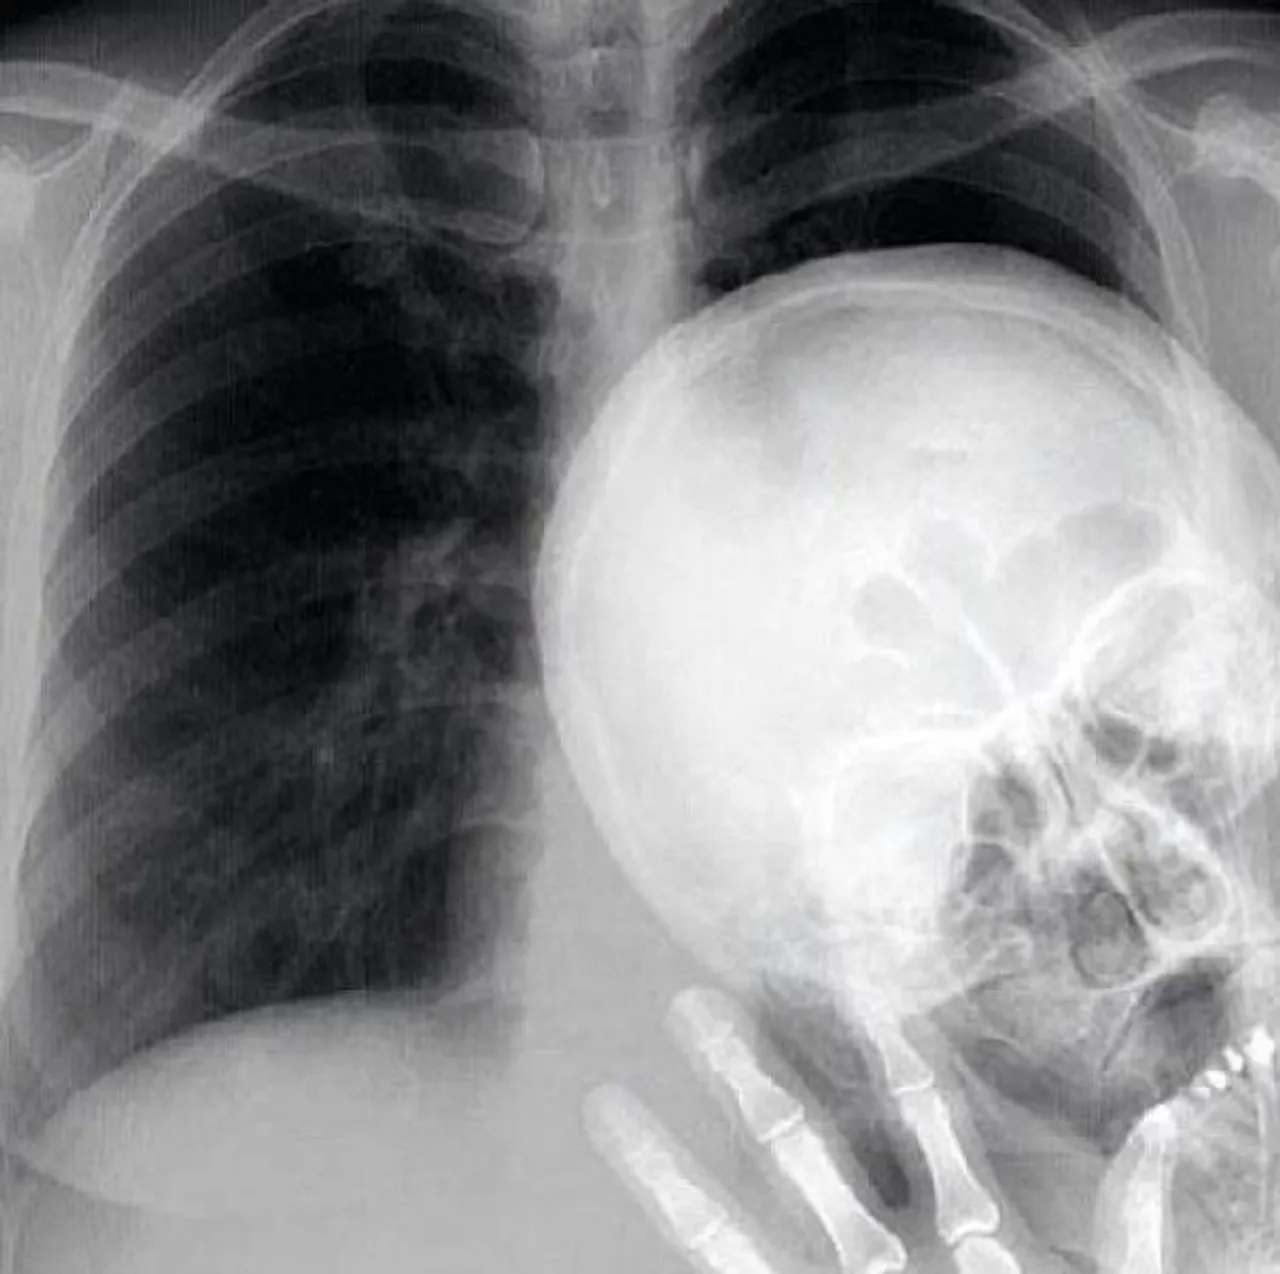

Foto: izismile.com

2/16